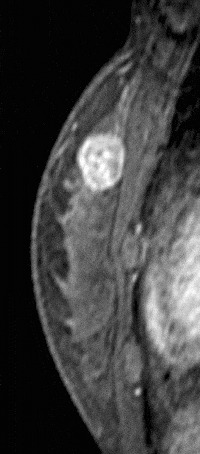

Internal enhancement of masses can be described as homogeneous or heterogeneous. Homogeneous enhancement is confluent and uniform (Fig. 8). Heterogeneous enhancement is non-uniform with areas of variable signal intensity (SI) (Fig. 9). Heterogeneous enhancement can be further classified as rim (Fig. 10), dark internal septations (Fig. 11), enhancing internal septations (Fig. 12) or central enhancement (Fig. 13).

Figure 12. Enhancing internal septations. Pathology – Invasive ductal cancer.

Figure 13. Centrally enhancing mass. Pathology – Invasive ductal cancer.